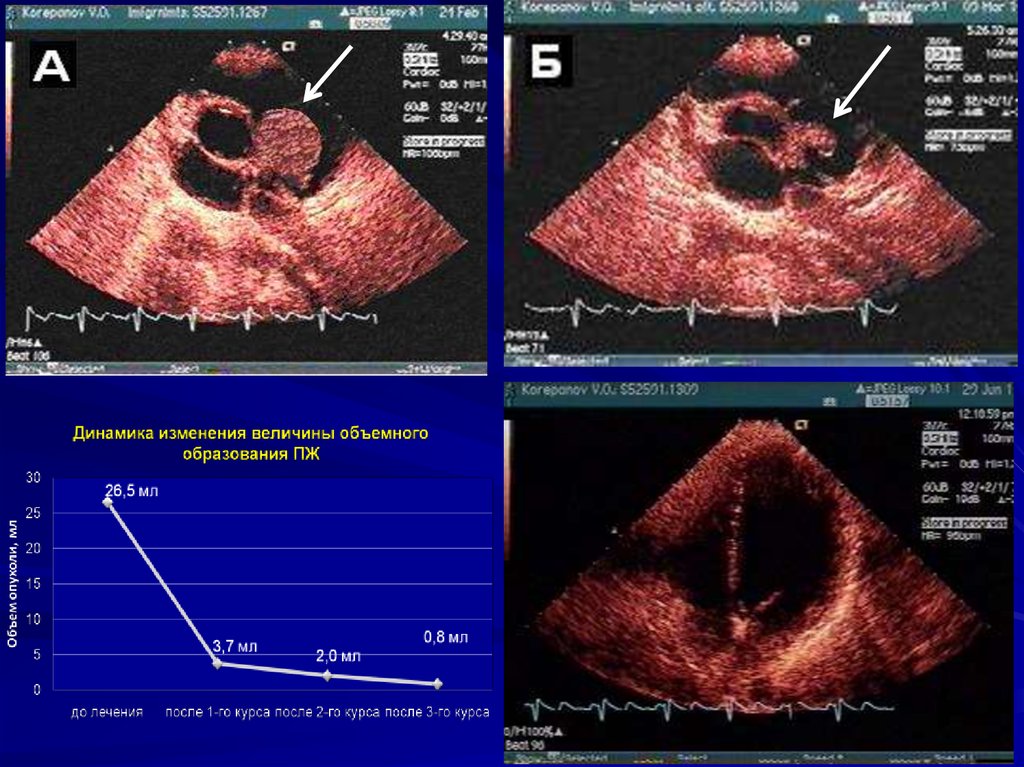

9. ЭХО-КГ больного К. исходно

4-камерная позиция от верхушки

Парастернальная позиция по короткой оси

В январе 2010 г начата химиотерапия по схеме CHOP-14

циклофосфан 1200 мг,

доксорубицин 80 мг,

винкристин 2 мг,

преднизолон 60 мг

+ плановое введение колониестимулирующих факторов с 9-го по

13-й день, возобновление цикла на 15-й день